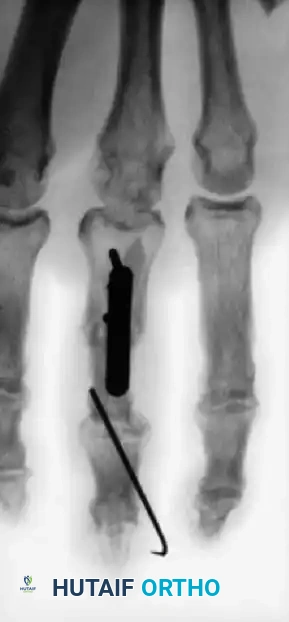

Fig. 64-5 Various techniques employed to manage middle phalangeal fractures in multidigit replantation. Combination intramedullary Kirschner wire rod and wiring in index fi nger and intraosseous wiring alone in middle fi nger with good rotational control.

Figure 64-5: Advanced Wiring Techniques.

Various techniques employed to manage middle phalangeal fractures during a complex multidigit replantation. Note the combination of an intramedullary Kirschner wire rod with supplemental wiring in the index finger, and intraosseous wiring alone in the middle finger, both achieving excellent rotational control.